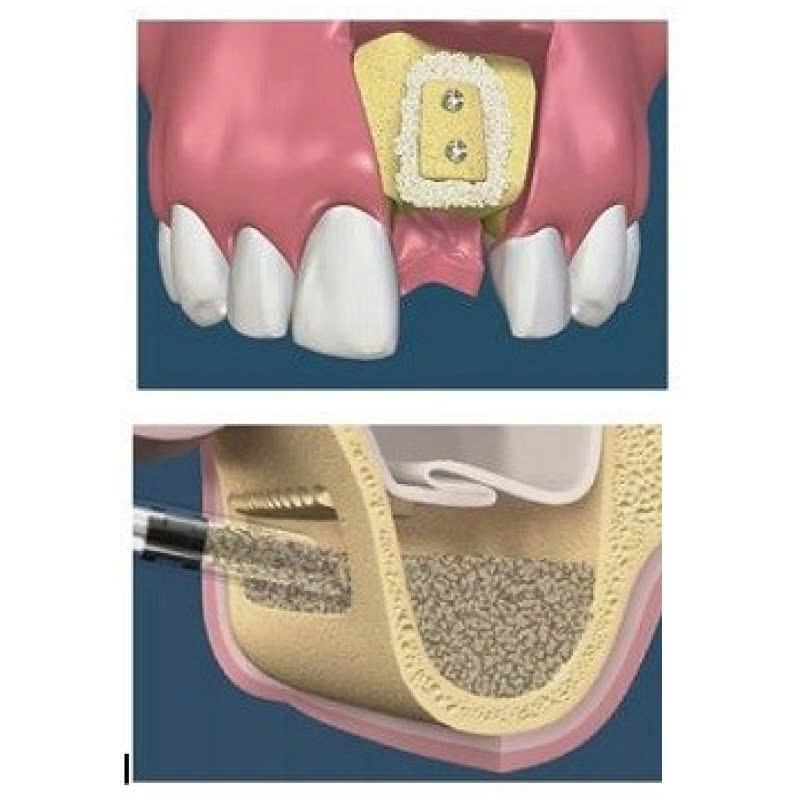

Nâng xoang kín là phương pháp nâng xoang từ bên trong, qua lỗ cấy Implant. Trong quy trình này, bác sĩ sẽ mở một đường rạch nhỏ trên nướu, tạo lỗ để có thể tiếp cận vùng xoang hàm và nâng màng xoang lên. Sau đó, xương hàm cần phải cấy ghép sẽ được đưa vào để có thể lấp đầy khoảng trống.

Bước 3: Mở đường rạch

Bác sĩ sẽ mở một đường rạch nhỏ, khoảng 3-6mm phía dưới chân răng, để tiếp cận vùng xoang hàm.

Bước 4: Nâng màng xoang

Sau khi mở đường rạch, bác sĩ sẽ cẩn thận nâng màng xoang lên cao.

Bước 5: Ghép xương

Tiếp theo, xương được đưa vào lấp đầy khoảng trống ở vùng xoang hàm.